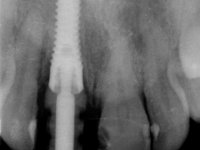

After the impression of the implant using a double-mix technique with double viscosity and the collection of shape and color information by the ceramist, we proceed with the work. In the model, a syn octa was placed over the implant, and a screw was placed on it to assess its emergence in relation to the incisal edge. Then, an adequate emergence profile in the artificial gingiva was prepared. A abutment with characteristics suitable for overbite and simultaneously capable of receiving a veneer was waxed on top of this scenario. This waxing gave rise to the manual milling of a very personalized abutment. An infrastructure in Zr was also made for the veneer with a very great adaptation to the abutment. On this infrastructure ceramics were placed. Ceramic fluorescence sought to compensate for the lack of fluorescence that Zr had and obviously further customize the aesthetics. The adhesive bridge was removed and the definitive work was placed. The syn octa was initially tightened with 35 N to the implant and then the Zr abutment was tightened over the syn octa with 15 N. The access hole was plugged and then the veneer was cemented with resin-reinforced glass ionomer. After 15 years, the patient returned to the consultation with tooth mobility. Fortunately, nowadays we have the possibility of having dynamic tightening wrenches that allow tightening screws with greater inclinations. An access cavity was made without damaging the incisal edge of the veneer. Tightening was done with a dynamic wrench with 15 N torque. The hole was covered with Teflon and filled with composite resin. This solution allowed the problem to be solved in a simple and economical way.